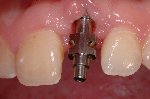

- Vollkeramische Restauration auf Implantat

- Vollkeramische Restauration auf vollkeramischen Abutment